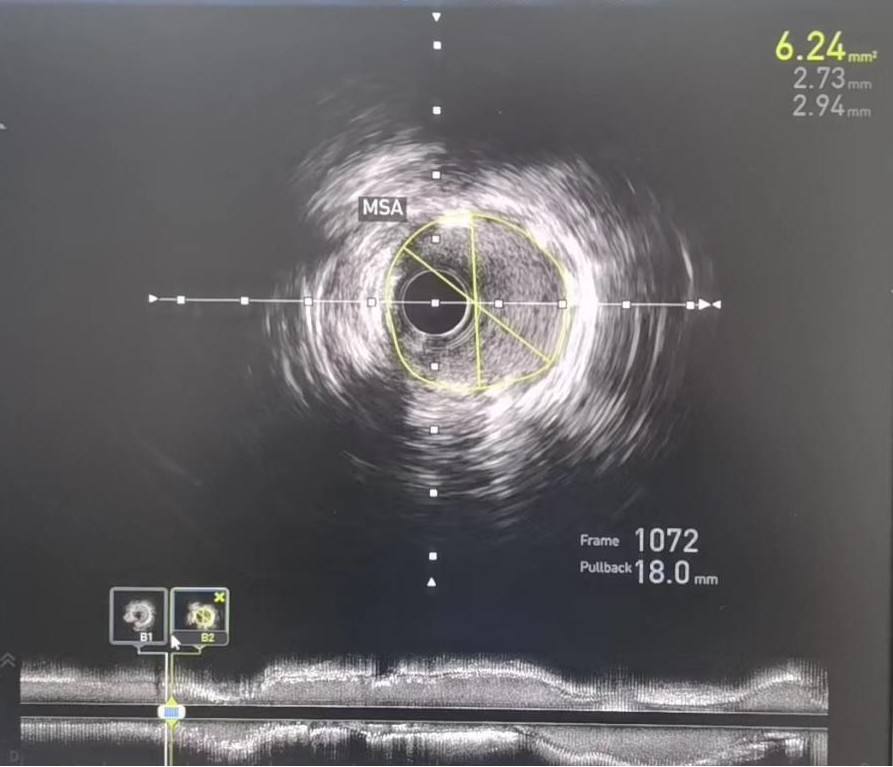

术后:IVUS-前降支支架植入后

考虑无法使用造影剂进行支架定位,如何将支架定位到理想的位置,成为手术的最大难点。专家团队应用血管内超声的换能器作为路标,精确测量所需支架长度及直径,在透视下,完美将支架释放于理想位置,于右冠顺利植入支架与原有支架串联。“打通”了冠脉狭窄通路,实现了右冠脉血运的重建,再次复查IVUS显示支架位置完美,膨胀、贴壁良好,病变被完全覆盖且左冠病变无进一步处理指征,全程未使用造影剂,恢复良好。